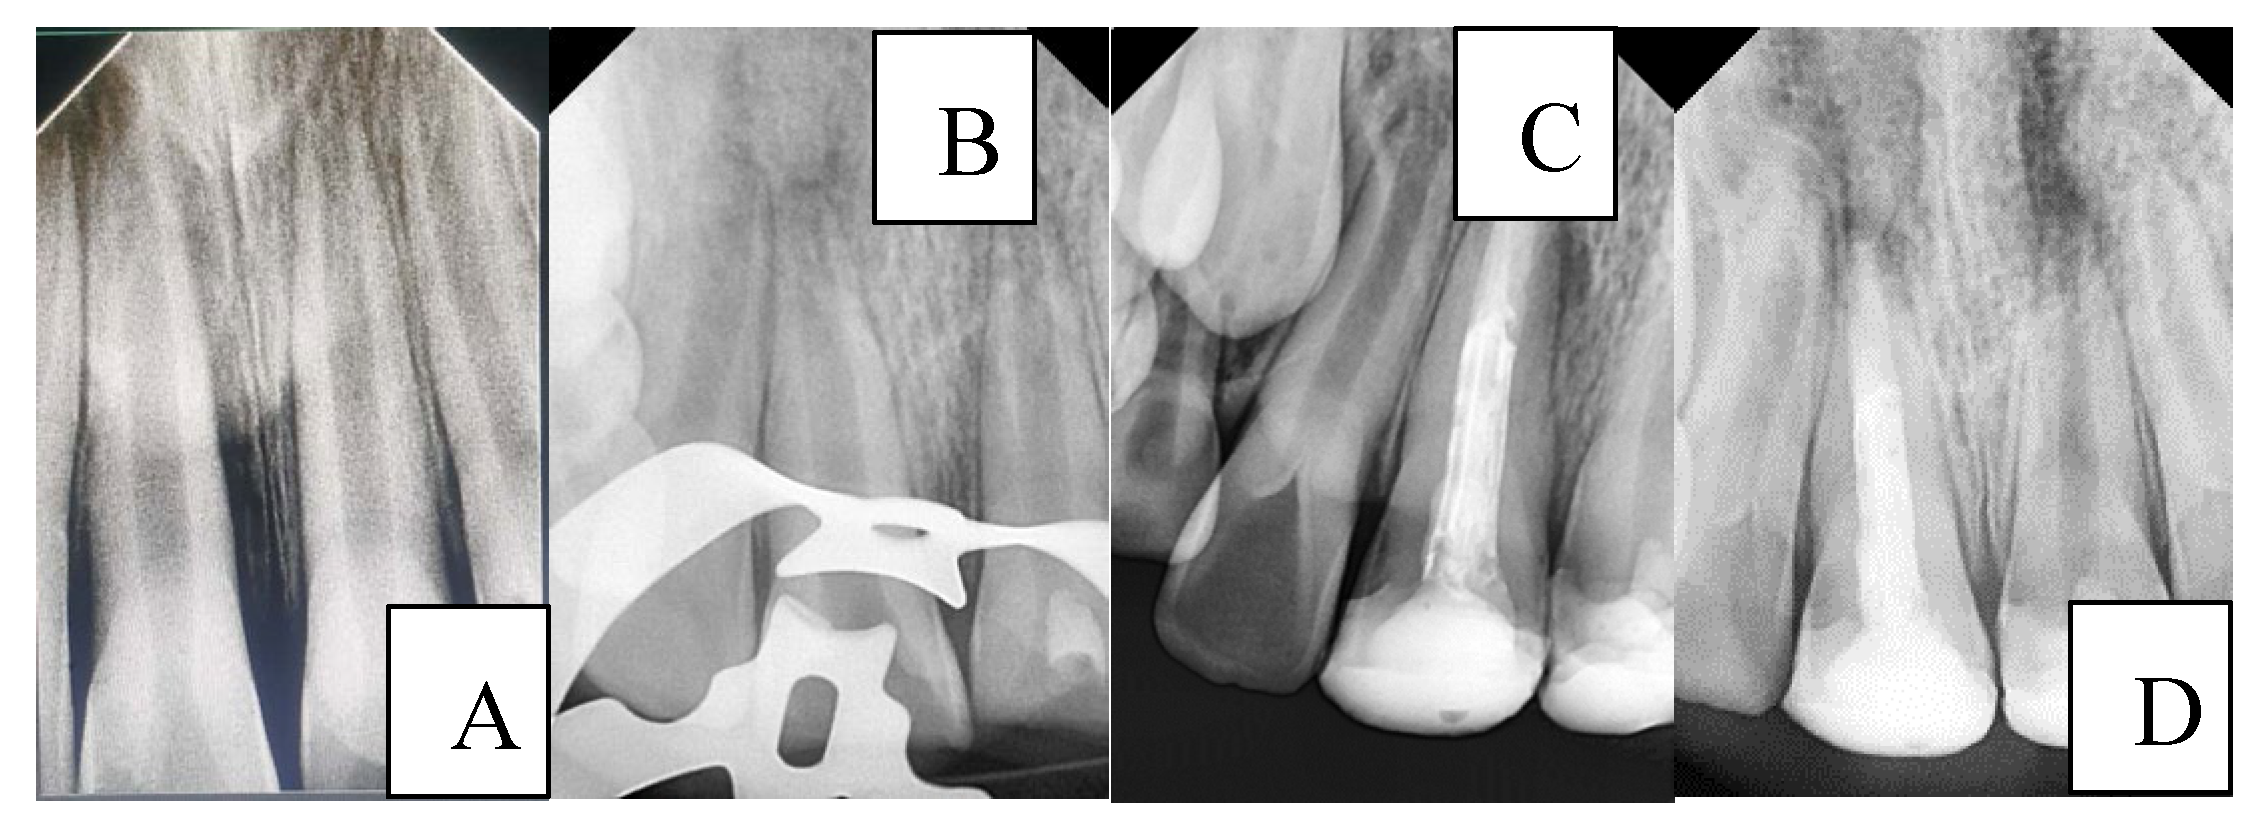

Figure 5. A case of managing anterior teeth with a history of repeated trauma: A: Diagnostic radiograph, B: Radiograph showing working length determination for tooth #11 and MTA pulpotomy for tooth #21 C: Radiograph showing the placement of MTA apical plug and final restorations, and D: Two-year follow-up radiograph showing successful treatment outcome of tooth #11 and failure of tooth #21.

A 9-year-old child presented to the Department of Pediatric Dentistry with a history of recurrent dental trauma. The first injury, one year prior, had resulted in an uncomplicated crown fracture of tooth #11, still untreated. In contrast, the second trauma, one month earlier, caused an uncomplicated crown fracture of tooth #21. The child’s main complaint was pain associated with tooth #21. Routine radiographic examination revealed pulp necrosis in tooth #11. A vital pulp therapy using MTA was performed on tooth #21, whereas tooth #11 was managed with an MTA apical plug.

A two-year follow-up radiograph showed a marked reduction in the periapical radiolucency of tooth #11 and the formation of a mineralized apical barrier adjacent to the plug. In contrast, tooth #21 later developed symptoms of acute apical periodontitis, necessitating additional endodontic intervention.